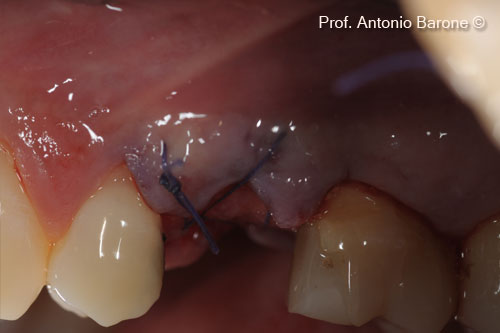

Hình ảnh lâm sàng mặt ngoài của ma trận Derma được cấy ghép vào mặt ngoài bằng vạt bao

Hình ảnh lâm sàng nhìn từ phía má của miếng ghép Derma được gấp về phía vòm miệng và cố định bằng các mũi khâu tự tiêu